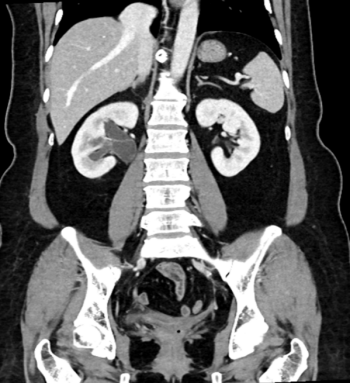

术后半年复查积水缓解

术后半年复查积水缓解(憋尿状态)